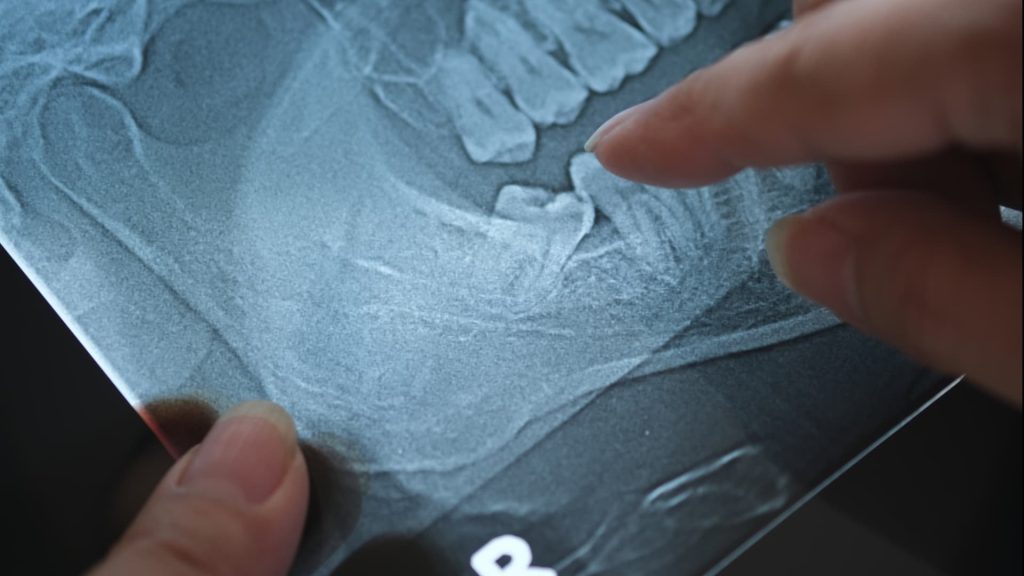

While dentists always aim to save natural teeth whenever possible, sometimes removal is the healthiest choice. Common reasons for extraction include severe decay, advanced gum disease, fractures below the gumline, or impacted wisdom teeth that threaten neighboring teeth.

There are two main types of extractions. A simple extraction is performed when the tooth is visible and can be removed with standard instruments. A surgical extraction is required if the tooth is broken, impacted, or not fully erupted, and may involve small incisions or sectioning the tooth for safe removal.